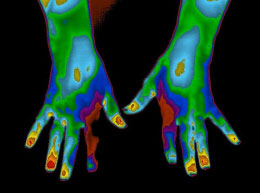

Advanced Thermal Imaging of West Michigan defines clinical thermography, also known as infrared imaging, as “specific evaluation of skin temperature patterns, which may reflect normal or abnormal functions of the body.” Clinical thermography has provided helpful assessment of many different ailments and diseases, such as diabetes, breast cancer, headaches, arthritis, and neck and back problems. To learn more about breast thermology, watch the video below.